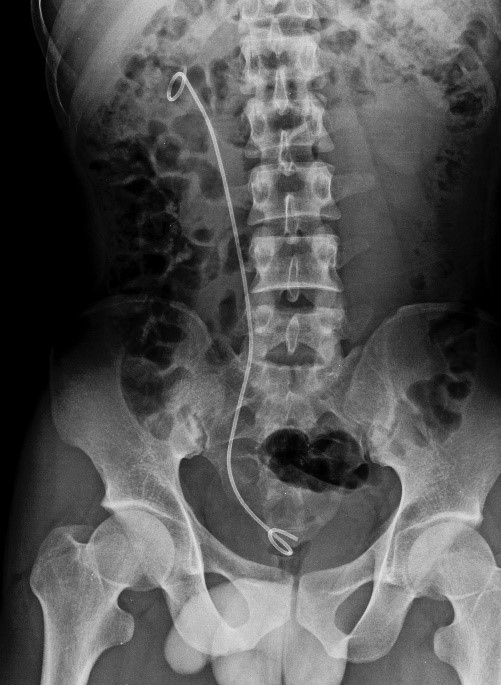

2.3. Cistoscopia (colocación de doble J)

Introducción de un cistoscopio a través de la uretra hasta la vejiga para la exploración de la misma (en busca de tumores, divertículos o cálculos), para la toma de biopsias o colocación de catéteres uretrales (ver modulo 16 donde los tenéis clasificados y explicados).

Suele realizarse de manera ambulatoria, normalmente con cistoscopio flexible porque el paciente lo tolera mejor, ya que normalmente se procede sin anestesia o con anestesia tópica. En algunos casos se realiza antes de una intervención abierta o laparoscópica o de manera combinada en quirófano.

El paciente se coloca en posición de litotomía y se necesitara la torre de “laparoscopia”, cistoscopio rígido o flexible (a elección del cirujano).

En caso de realizarse para la colocación de un catéter tipo doble J el procedimiento y preparación será el mismo que para la RTU, pero en vez del resector se preparará el cistoscopio (normalmente el compacto), hará falta una guía sensor, arco de RX (con funda estéril) y contraste. Tener a mano el catéter de elección del cirujano. Al finalizar la intervención se dejará al paciente sondado con una sonda tipo Dufour por si necesitase suero lavador, pero en principio saldrá sin él (acordarse de poner tapón en la vía de entrada de suero).

Imagen 93. Colocación de Catéter doble J.